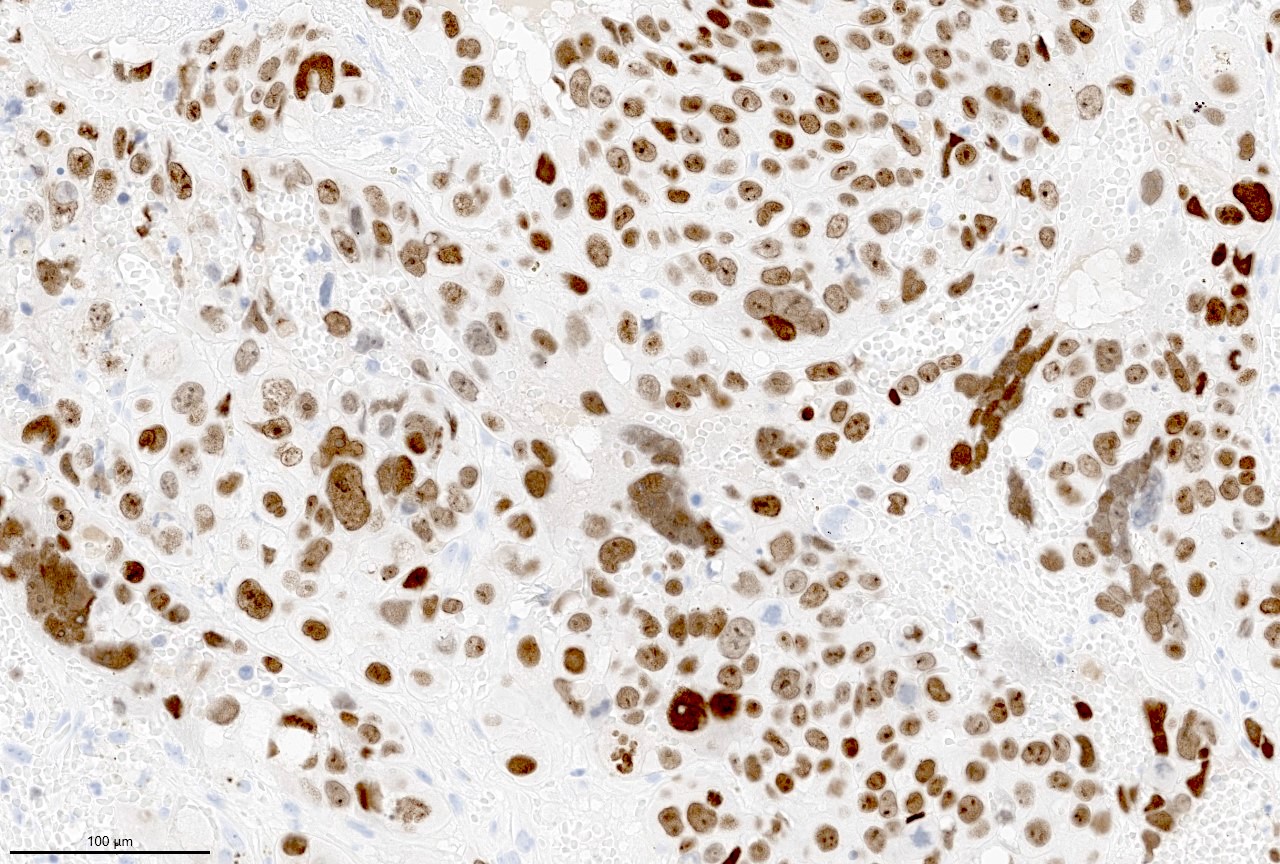

- Beta hCG immunohistochemical stain highlights cells with trophoblastic differentiation

Microscopic (histologic) images

- Beta hCG: syncytiotrophoblasts and intermediate trophoblasts